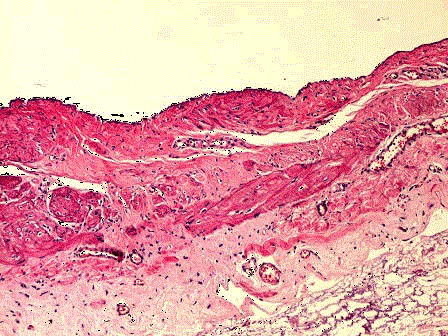

问题 男性,67岁,左侧睾丸疼痛肿胀一年,行左睾丸附睾切除术。大体见附带精索、鞘膜的睾丸和附睾8cm×6cm×5cm,囊性,切开鞘膜有约60ml淡黄色液体,鞘膜壁明显增厚。镜下见鞘膜囊壁衬覆一层扁平间皮细胞,其下为纤维结缔组织(如图)。应诊断为 ( )

选项 A.睾丸精原细胞瘤 B.睾丸卵黄囊瘤伴囊肿 C.睾丸囊性畸胎瘤 D.睾丸鞘膜积液 E.以上均不是

答案 D